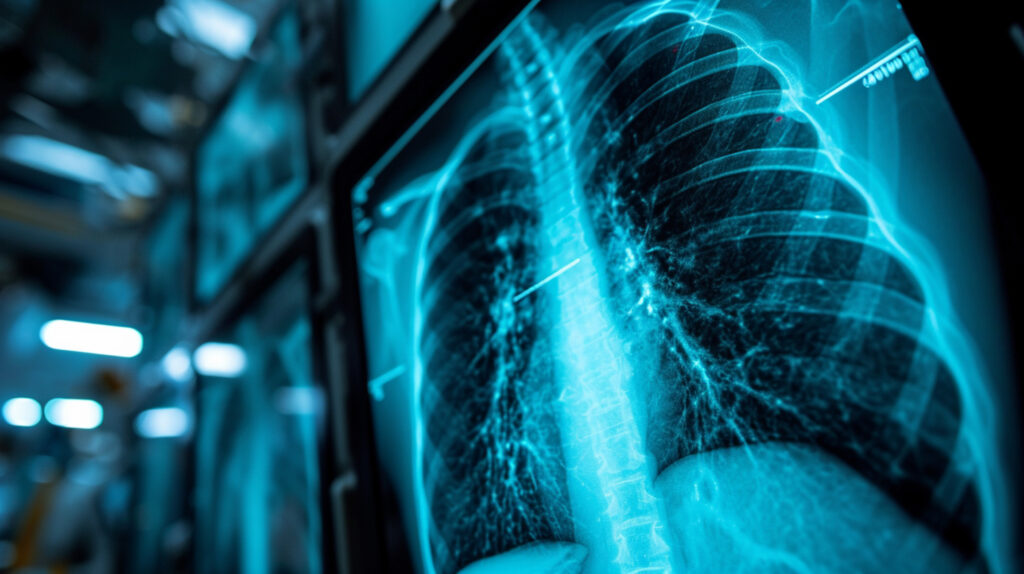

This study presents a novel approach to paediatric age estimation using chest X-rays and deep learning. Age assessment is a crucial component of monitoring growth and development in children, with wrist radiographs being the standard imaging method for evaluating bone age. The authors highlight that chest X-rays are already the most frequently performed radiological examination in paediatric care, making them an abundant and accessible source of diagnostic data. By applying artificial intelligence to this existing resource, additional imaging can potentially be avoided, lowering radiation exposure while providing valuable clinical insights.

Attention heatmaps revealed that the model focused on anatomical areas, including the spine, mediastinum, heart, great vessels, and surrounding bones. These findings suggest that both skeletal and soft tissue features contribute to age estimation in chest radiographs.